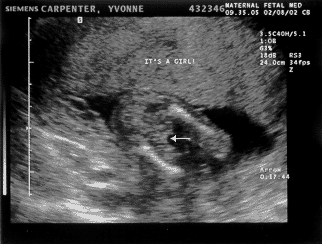

I am getting big! Matt: Amniocentesis day! This is the big daddy of tests. Although I was there I can’t comment on how it went since the needle was not in me. At one point I got up to hold Yvonne’s hand but the doctor kindly asked me to sit down. Seems that some dads pass out and they don’t want any cracked skulls on their hands. Before the big poke however the MY baby went trough a battery of measurements via ultrasound. My, how we have grown! As this scan shows we are looking downright human in there. Also I won’t have to call the MY baby two names every time I talk to it because we found out the answer to that little question. However since Yvonne was the one getting stuck I will let her have the pleasure of sharing the news. At any rate, all measurements came back normal and we will get the results of the amnio in 8-10 days.

It's a girl! Yvonne: Phew! I am glad we are over the amnio hump. It was not exactly painless, but it wasn’t nearly as painful as I imagined it. I got 3 pokes, 2 from the anesthetic and 1 from the real needle. The whole thing was done in about 3 or 4 minutes and after I got a “beep-beep” band-aid on my “owy” we were presented with 2 little tubes of yellowish liquid. I confirmed that the name on the tubes was mine and off they went to the lab. The exciting part though was the ultrasound done before the test. They turned the baby upside down (so to speak) measuring every little piece of its body and looking for anything suspicious. There seems to be quite a few things that can go wrong and still take a baby this far into the pregnancy, but thankfully nothing was found — and it wasn’t for lack of searching!! For example, they spent almost 5 minutes on the spine alone, checking every set of 2 or 3 vertebras to make sure they looked right and did not have a gap. Kyla passed this part of the test and gave us a thumbs up on one of the ultrasound views:-) You read it right, no more Luke/Kyla — for now on (95% sure anyway) it is Kyla only!! Luke will have to wait for his turn!